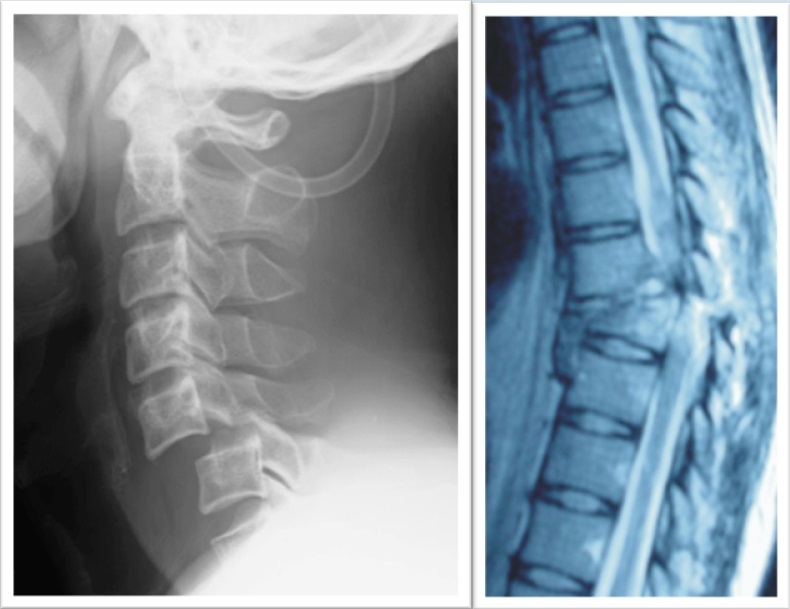

「iPS細胞を用いた脊髄損傷の再生医療」